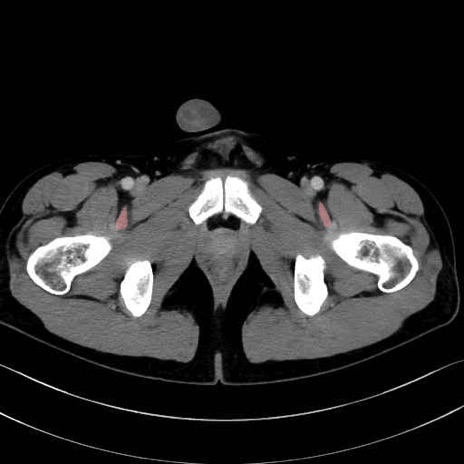

6. 大腿内側(内転筋群)

恥骨筋 (Pectineus)

長内転筋 (Adductor longus)

短内転筋 (Adductor brevis)

大内転筋・小内転筋 (Adductor magnus / Adductor minimus)